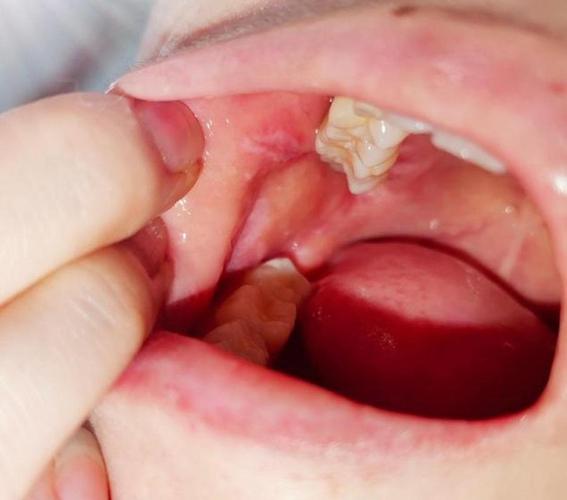

软腭:

(图片来源网络,侵删)- 危险性: 较高,位于口腔顶部,软的部分。

- 特点: 此处黏膜也较薄,发生糜烂型扁平苔藓时,疼痛和不适感明显,癌变风险也需警惕。